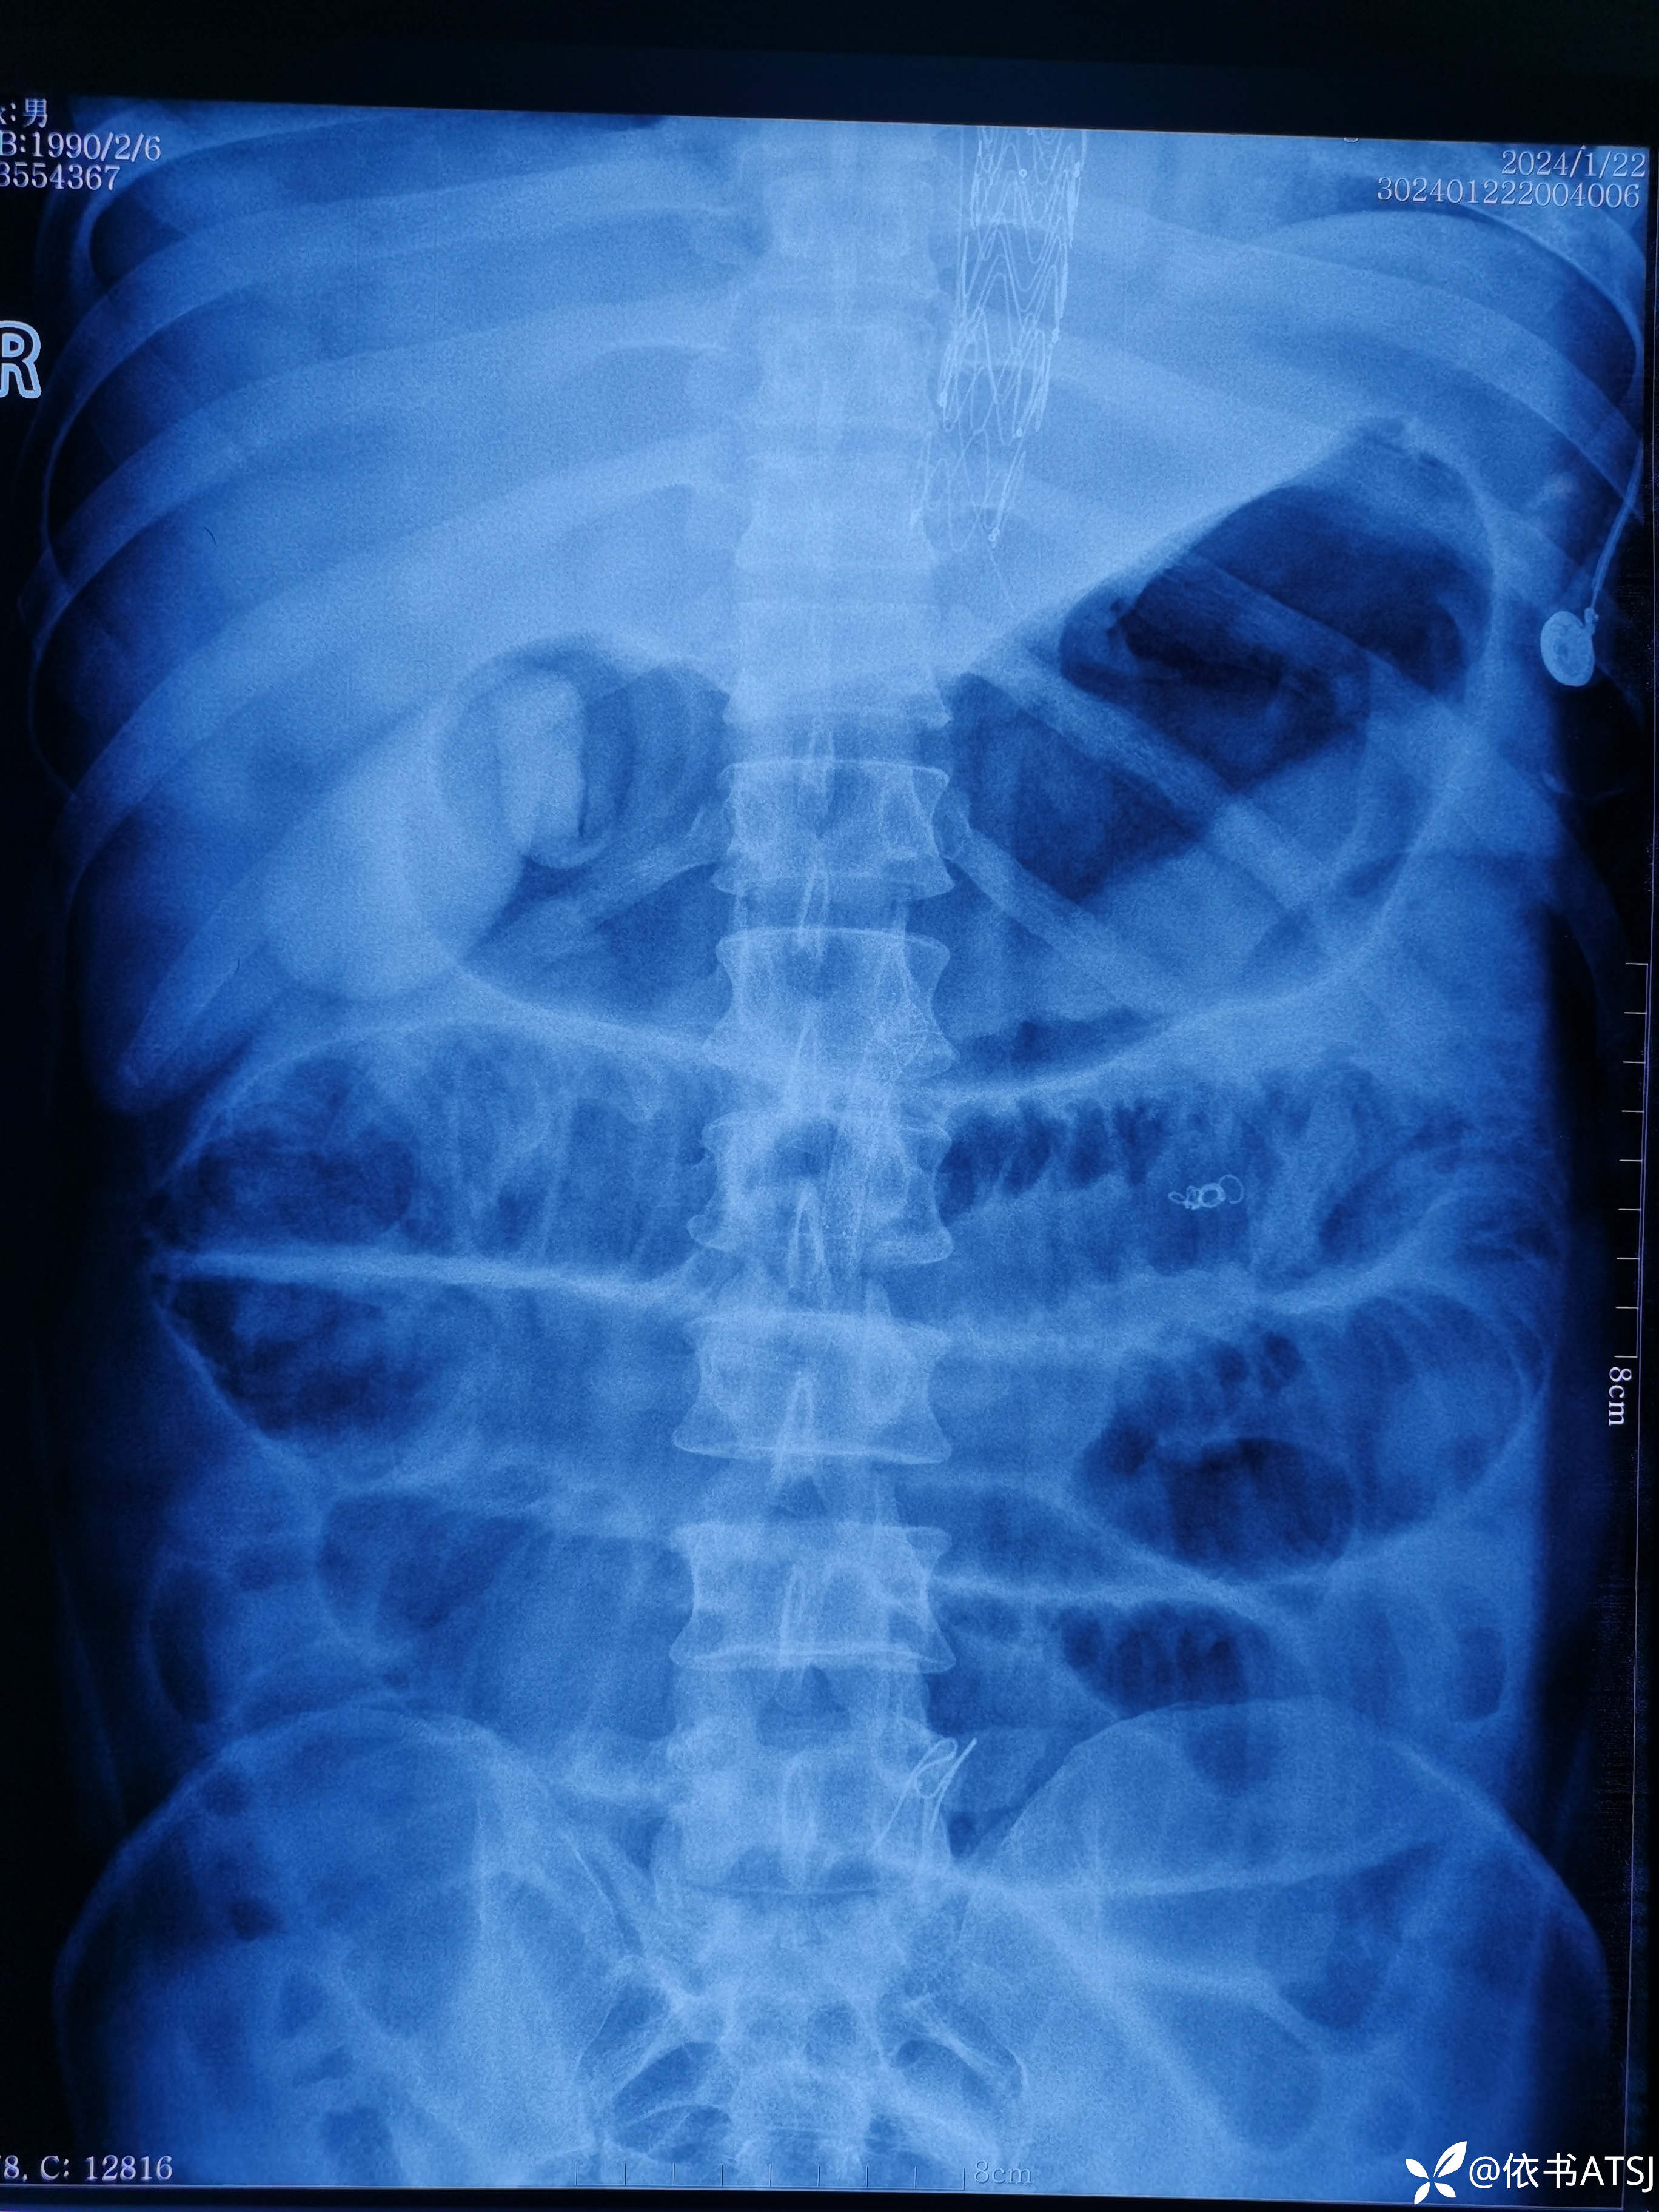

升主动脉-腹主动脉全程增粗,多个破口,累及肠系膜动脉、髂总动脉、髂内髂外动脉

讨论:本例患者,34岁,体型肥胖,高血压3年余,未重视,未系统诊治,突发胸腹部疼痛入院,虽然放了根长长的支架,命保住了,尿量也不错,可是血肌酐高,短期内脱离不了透析,针对这一年轻患者的全程广泛主动脉撕裂、多个破口,各位老师,您认为非常有必要排查血管炎这一疾病吗?